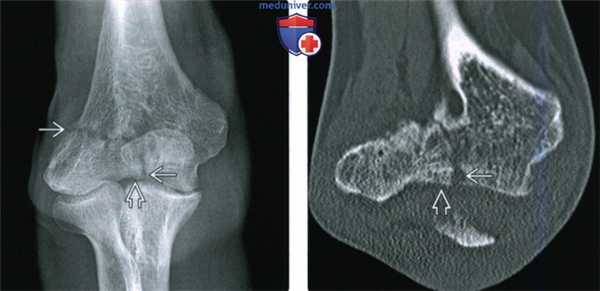

(Слева) На передне-задней рентгенограмме перелома латерального мыщелка Милча II у взрослого пациента визуализируется линия перелома В, переходящая на локтевой сустав медиальне латерального блокового гребня. Переломы Милча II встречаются чаще, чем I тип.

(Справа) На фронтальной КТ с реформатированием у этого же пациента входная точка перелома визуализируется лучше. При локализации перелома медиальне латерального блокового гребня В он визуализируется лучше, так как повреждение Милча II типа и поэтому оно сопровождается нестабильностью локтевого сустава.

(Слева) Фронтальная КТ с реформатированием у этой же пациентки помогает лучше оценить суставную поверхность. Перелом медиального мыщелка переходит на сустав латеральнее латерального блокового гребня, что относит его к повреждению Милча II типа, подразумевающее нестабильность. Кроме этого, при КТ была детально визуализирована деформация сустава.

(Справа) На передне-задней рентгенограмме у мужчины 60 лет с хронической болью в локтевом суставе можно видеть хроническое несрастание перелома медиального мыщелка. В локтевом суставе имеются легкие дегенеративные изменения.